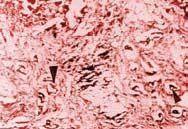

Histológicamente los cortes de los ratones sacrificados el día 1 (24 horas postobstrucción), mostraron congestión sinusoidal y vascular a nivel de los vasos portales con estasis biliar asociada en 20% de los cortes. Estas lesiones se consideraron como leves (figuras 1a, 1b). Los cortes obtenidos el día 7 mostraron acumulación de pigmento biliar en colangiolos y zona pericolangiolar, con proliferación portal de colágeno en 60% de los cortes. Estas lesiones sumadas a las consideradas leves, se refieren como lesiones moderadas (figuras 1c, 1d). En los cortes de los tejidos de los ratones sacrificados el día 15 postobstrucción, además de las lesiones observadas en los días 1 y 7, se encontró proliferación hamartomatosa de colangiolos y fibrosis portal en conductos biliares, placa limitante y lóbulos en 15% de los cortes. Estas lesiones se clasificaron como severas (figuras 2a, 2b, 2c, 2d). Las lesiones observadas a nivel de cerebro, corazón y pulmones se debieron a congestión vascular y dilatación en varios grados. Los riñones mostraron precipitación de pigmento biliar en los túbulos colectores al día 15 de sacrificio. El grupo control presentó morfología macroscópica y microscópica hepática normal.

Figura 1a. Morfología y organización del parénquima hepático bien conservado.

Figura 1b. Trombo biliar intracolangiolar (flecha grande) con proliferación conectiva concéntrica, repliegue de ducto epitelial (flecha mediana) y signos de esteatosis (flecha pequeña).